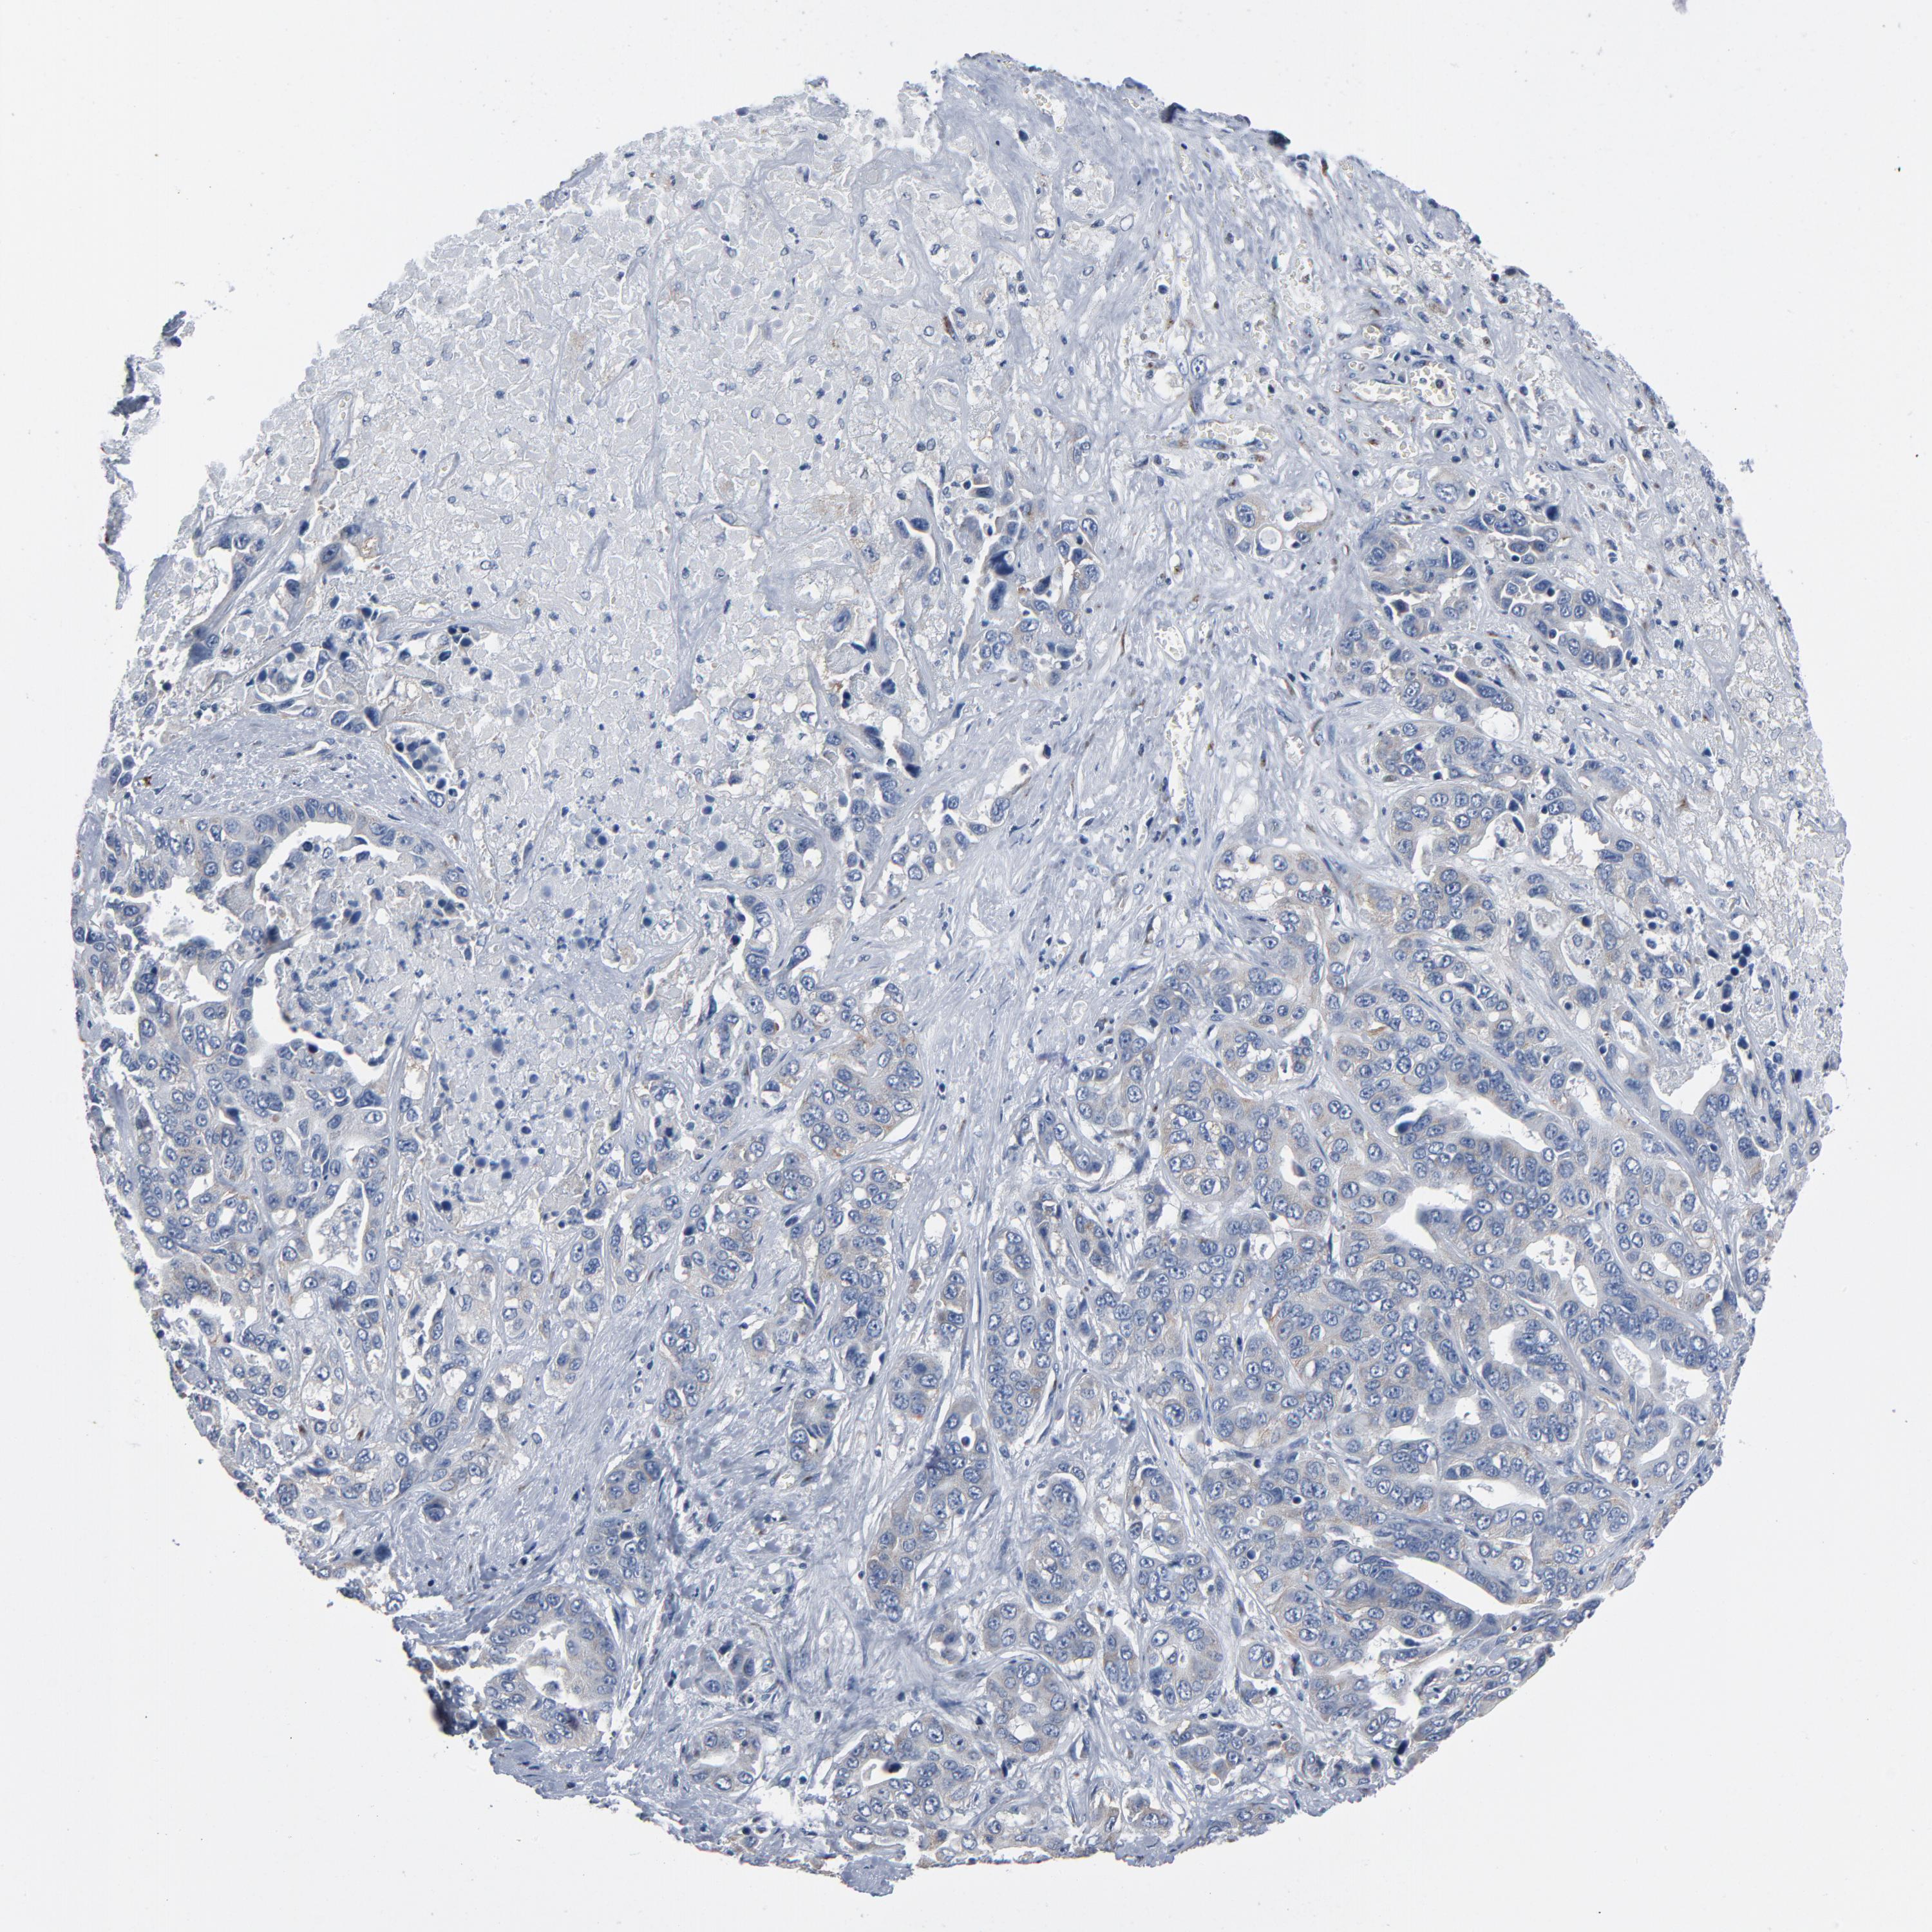

LIVER CANCER - Protein expressioni

A mouse-over function shows sample information and annotation data. Click on an image to view it in a full screen mode. Samples can be filtered based on level of antibody staining by selecting one or several of the following categories: high, medium, low and not detected. The assay and annotation is described here.

Note that samples used for immunohistochemistry by the Human Protein Atlas do not correspond to samples in the TCGA dataset.

Antibody stainingi

Antibody staining in the annotated cell types in the current human tissue is reported as not detected, low, medium, or high, based on conventional immunohistochemistry profiling in selected tissues. This score is based on the combination of the staining intensity and fraction of stained cells.

Each image is clickable and will lead to virtual microscopy that enables deeper exploration of all samples and also displays staining intensity scores, fraction scores and subcellular localization as well as patient and tissue information for each sample.

Antibody HPA003720

Staining

High

Medium

Low

Not detected

Intensity

Strong

Moderate

Weak

Negative

Quantity

>75%

75%-25%

<25%

None

Location

Nuclear

Cytoplasmic/membranous

Cytoplasmic/membranous,nuclear

Cholangiocarcinoma

Carcinoma, Hepatocellular, NOS